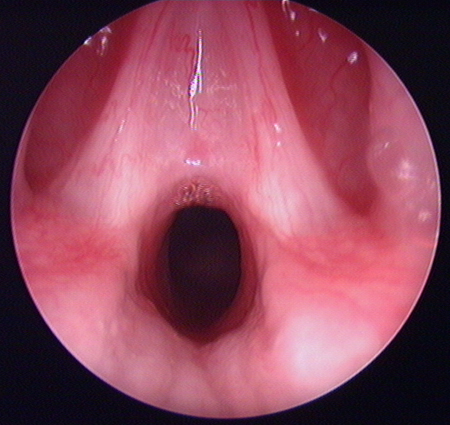

Glottic web

From the personal teaching collection of Simone J. Boardman, MBBS, FRACS (OHNS) and C. Martin Bailey, BSc, FRCS, FRCSEd